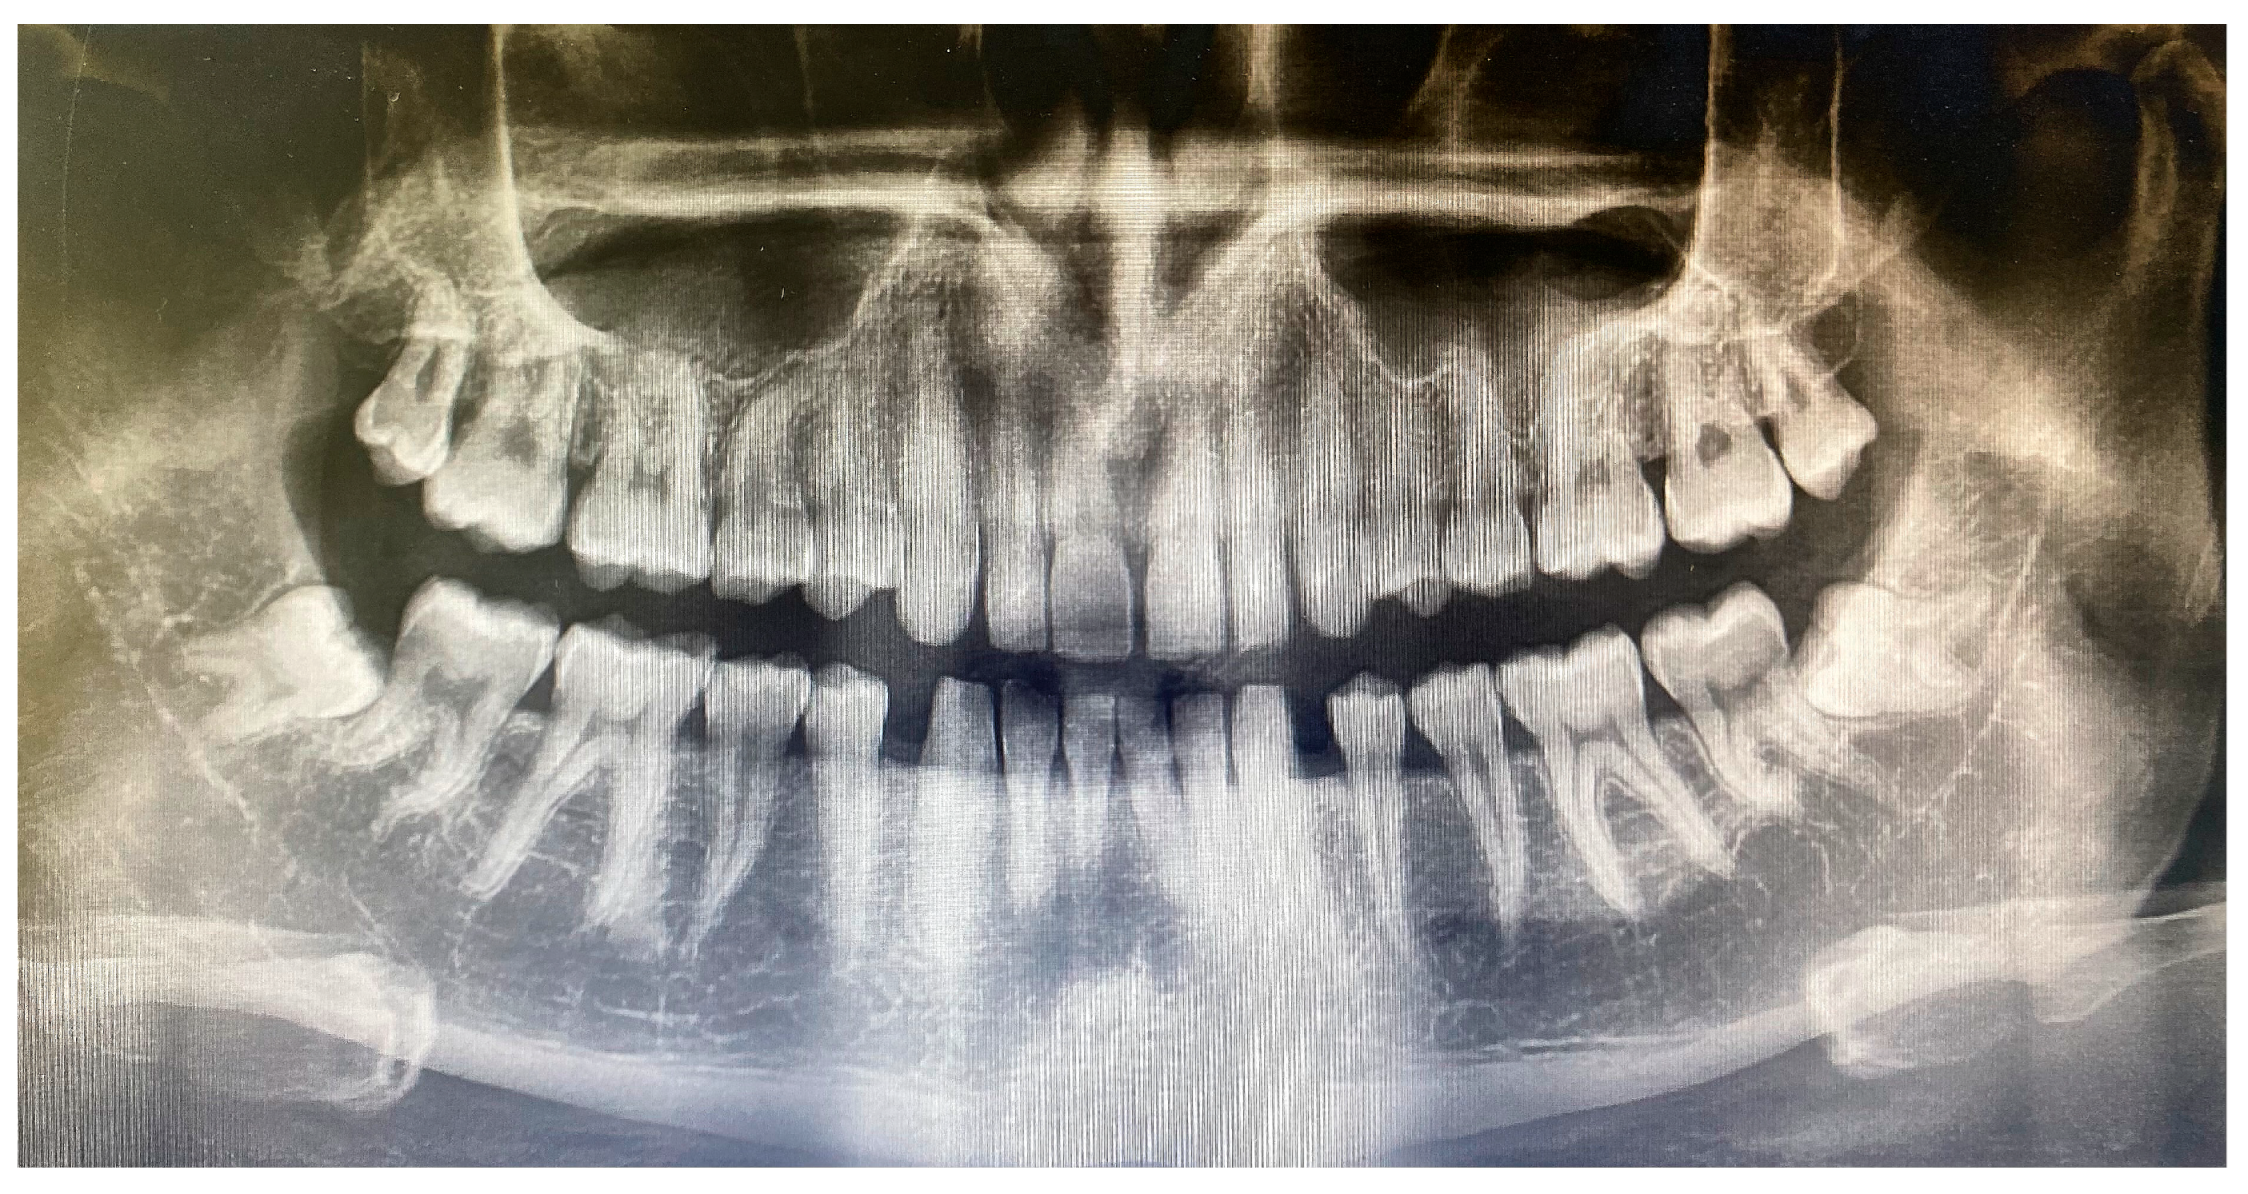

Comparative Investigation of Anti-Inflammatory Effect of Platelet-Rich Fibrin after Mandibular Wisdom Tooth Surgery: A Randomized Controlled Study

2. Materials and Methods

2.1. Operations